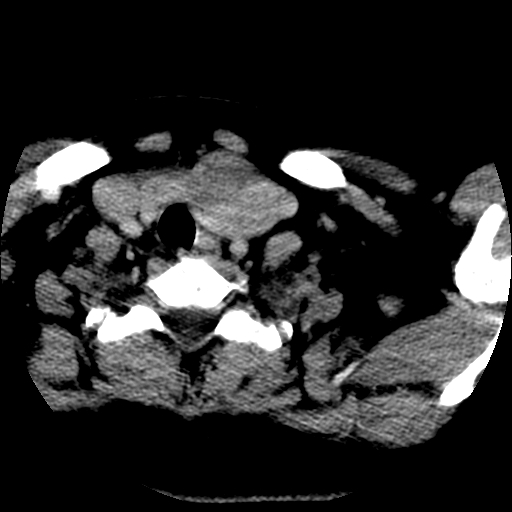

标题: CT25491:女,55岁,发现左侧甲状腺肿块一个月。 [打印本页]

女,55岁,发现左侧甲状腺肿块一个月,彩超示:甲状腺多发结节伴左叶结节液化。

腺瘤囊变

考虑左侧甲状腺腺瘤囊变。